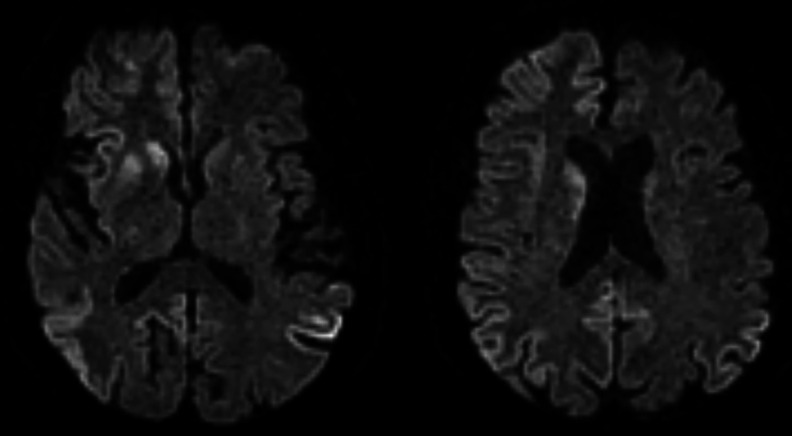

Case presentation: This case study presents a 68-year-old man with a 6-week history of progressive cognitive decline and behavioural changes, ultimately leading to a dire clinical state. The initial symptoms included confusion, intermittent headaches and episodes of aggression towards his wife, preceded by 2 weeks of visual hallucinations. On examination, the patient displayed an ataxic gait, with signs of cerebellar dysfunction. The clinical course evolved, marked by myoclonic jerks, culminating in a decline in both his Glasgow Coma Scale (GCS) score and overall clinical status.

Conclusion: The patient's rapidly deteriorating condition over 6 weeks was thought to be too rapid for sCJD, and the patient was treated initially as an LS. However, post-mortem biopsy findings confirmed CJD. Asymmetric periodic discharges on EEG, asymmetric neuroimaging changes and the manifestation of psychiatric symptoms should not preclude the diagnosis of sCJD. This case highlights the importance of recognising the potential rapid deterioration of sCJD, which would alert clinicians to earlier diagnosis and management.